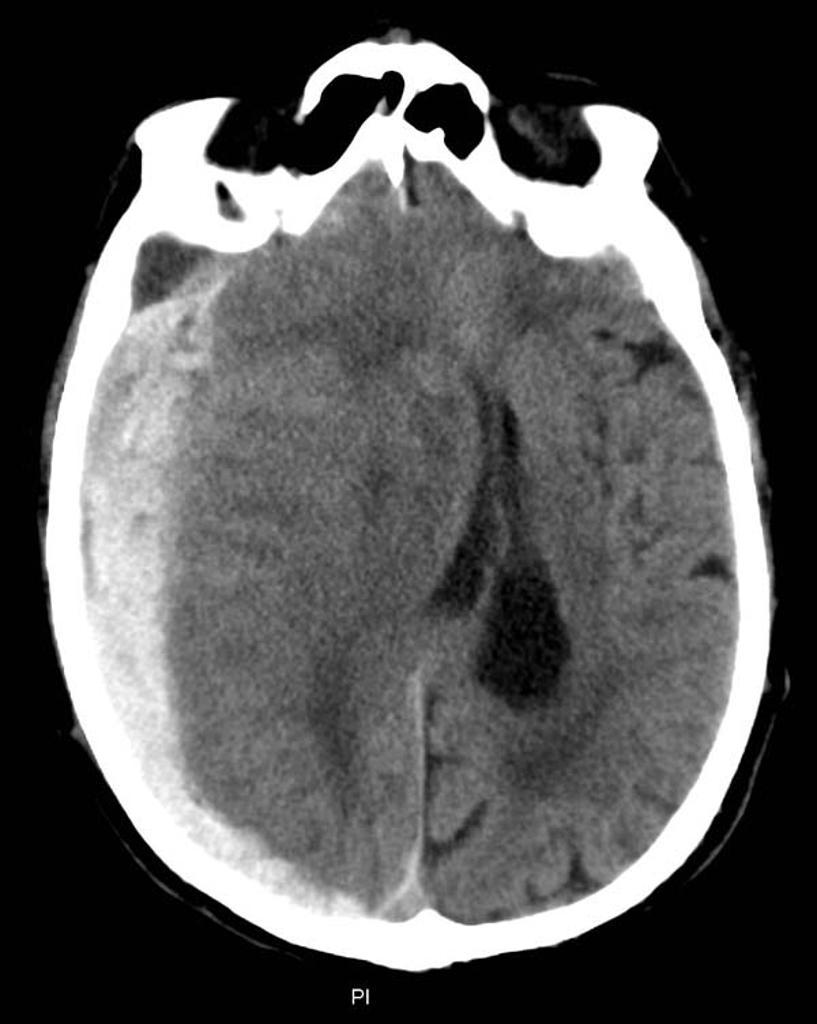

Subdural hematoma

• Hematoma between dura and arachnoid

• Occurs in any age group, usually after trauma

• Stretching and tearing or bridging cortical veins due to sudden change in velocity of head (shearing forces)

• Crescent-shaped

• Usually more extensive than EDH

• Not limited by sutures; are limited by dural reflections (falx cerebri, falx, cerebelli, tentorium

• Most unilateral in adults vs. bilateral in infants

• Subacute = Isodense

• Acute = Hyperdense

• Indirect signs:

• Sulci do not reach the skull

• Apparent cortical thickening

• Mass effect including effacement of sulci, midline shift

• Chronic = Hypodense

• May change to biconvex shape